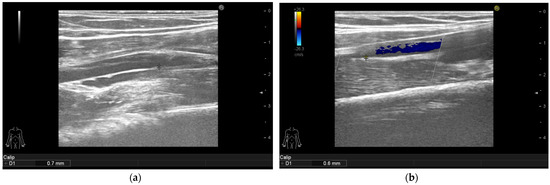

3.4. Ultrasonographic Findings

| Arterial Intima Media Thickness | Baseline Median (IQR)  | 6-Month Follow-Up Median (IQR) | p-Value |

| Intima media thickness of the right carotid arteries (mm) | 1.1 (1.0–1.3) | 0.8 (0.6–0.9) | <0.001 |

| Intima media thickness of the left carotid arteries (mm) | 1.1 (0.9–1.35) | 0.7 (0.6–0.9) | <0.001 |

| Intima media thickness of the right brachial arteries (mm) | 0.75 (0.6–0.9) | 0.6 (0.5–0.7) | <0.001 |

| Intima media thickness of the left brachial arteries (mm) | 0.8 (0.6–0.9) | 0.5 (0.5–0.7) | <0.001 |

| Intima media thickness of the right femoral arteries (mm) | 0.9 (0.8–1.05) | 0.7 (0.5–0.9) | <0.001 |

| Intima media thickness of the left femoral arteries (mm) | 0.8 (0.6–1.1) | 0.7 (0.5–0.8) | <0.001 |